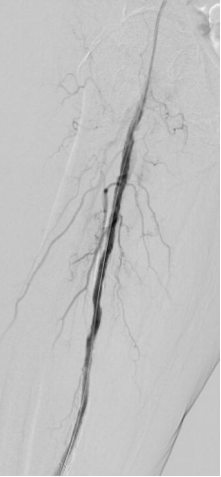

1. 术前造影:

4. 开通胫前-足背动脉

5. 选择6*60mm Shockwave冲击波球囊处理股腘动脉

6. 股浅动脉下段置入6-150mm载药支架,于股浅动脉中上段置入6-220、 6-150mm载药球囊扩张

7. 术后造影血流恢复